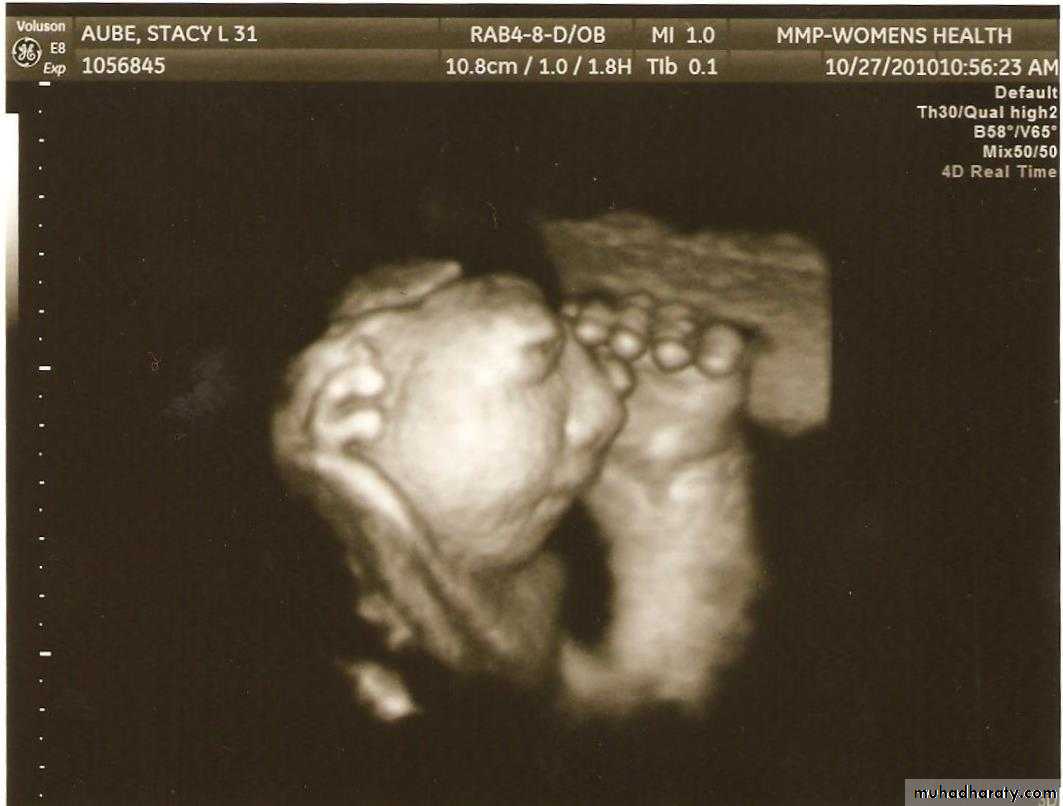

Anenecephaly >>>> frog sign appearance :

Anencephaly is the most severe form of cranial neural tube defect (NTD) and is characterized by absence of cortical tissue (although brainstem and cerebellum may be variably present) as well as absence of the cranial vault.Associations

Anencephaly may be sonographically detectable as early as 11 weeks. Ultrasound can be a non invasive,

no parenchymal tissue is seen above the orbits and calvarium is absent: parts of the occipital bone and mid brain may be present urinary tract abnormalities: hydronephrosis most common